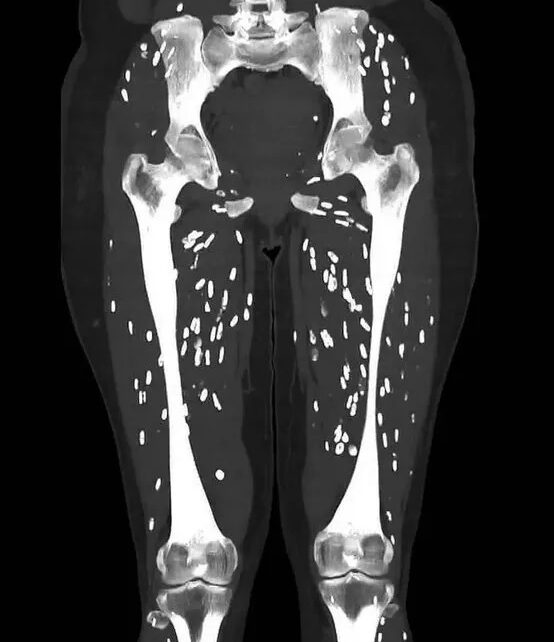

શું તમે જાણો છો કે કાચું પાકેલું માંસ ખાવુ તમારા હેલ્થ માટે કેટલું જીવલેણ સાબિત થઈ શકે છે. થોડા સમય પહેલા એક વ્યક્તિના મગજમાં કીડા હોવાનું સામે આવ્યુંહતું. ત્યારે હાલમાં જ ડો.સૈમ પોતાના સોશિયલ મીડયા પર સિટી સ્કેનને એક તસવીર મૂકી તો આખી દુનિયા હચમચી ગઈ. આ સિટી સ્કેલનમાં એક દર્દીના ઘૂંટણમાં જીવતા કીડા ફરતા જાેવા મળ્યાં. આ કીડાને કારણે દર્દીના શરીરમાં ઈન્ફેક્શન થઈ ગયું હતું. તેણે જણાવ્યું કે, તેણે ડુક્કરનું કાચું પકાયેલું માંસ ખાધુ હતું. જેનાથી તેના પગમાં જીવિત કીડા પેદા થયા હતા.

આ સ્થિતિને ઈન્ટેસ્ટાઈન ટૈનિયાસિસ કહેવાય છે. ડોક્ટરે જણાવ્યું કે, આવી સ્થિતિમાં દર્દીના મગજ સુધી કીડા પહોંચી શકે છે. જેનાથી દિમાગમાં સિસ્ટ બની શકે છે. આવામાં માથાનો દુખાવો કે અન્ય ગંભીર ન્યૂરોલોજિકલ સમસ્યાઓનો સામનો કરવો પડી શકે છે. વાયરલ સિટી સ્કેનમાં જાેઈ શકાય છે કે, ચોખાના આકારના કીડા વ્યક્તિના પગમાં ચાલતા દેખાય છે. આ કીડા ઘૂંટણની આસપાસ ફરી રહ્યાં છે.

સિસ્ટીસકોર્સિસ એક પેરાસાઈટ ઈન્ફેક્શન છે, જે પોર્ક કે ટેપવોર્મને કારણે થાય છે. આ ઈન્ફેક્શન ત્યારે થાય છે, જ્યારે ટેપવોર્મ લાર્વા વ્યક્તિના ટિશ્યુ સુધી ઈન્ફેક્શન કરે છે. જેનાથી શરીરમાં સિસ્ટ બની જાય છે. ઈન્ફેક્શન ત્યારે થાય છે, જ્યારે કોઈ વ્યક્તિ દૂષિત ભોજન કે પાણીનું સેવન કરે છે. જેમાં કીડાના ઈંડા હોય છે. આ ઈંડા પેટમાં લાર્વા બની જાય છે. લાર્વા માંસપેશીઓ, મમગજ, આંખ જેવા શરીરના ભાગો સુધી પહોંચી જાય છે. તેના બાદ લાર્વા સિસ્ટ બની જાય છે, જે શરીર પર સોજાનું કારણ બને છે.